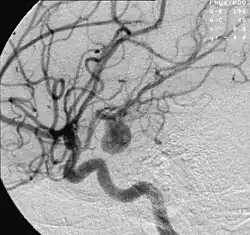

- Die Angiografie dient nicht nur dem Aneurysmanachweis, sondern wird zum Nachweis von Verschlusserkrankungen in peripheren oder zentralen Gefäßen wie etwa Nierenarterien begleitend eingesetzt.

- Bei der konservativen Therapie wird kein Eingriff vorgenommen, sondern das Aneurysma wird durch regelmäßige Kontrolle mittels bildgebender Verfahren (normalerweise Angiografien) beobachtet. Besonders bei kleinen nicht-symptomatischen Aneurysmen ist dies aufgrund des geringen Rupturrisikos eine Option.

- Bei der endovaskulären Therapie werden mittels eines hohlen Mikrokatheters über die Leistenarterie sogenannte Coils (Spiralen aus einer Platinlegierung) in den Aneurysmasack gebracht. Diese Coils füllen das Aneurysma zwar nur zu etwa 10 % bis 30 % aus, verursachen aber eine Thrombenbildung und verhindern so die weitere Blutzirkulation im Aneurysma und somit eine Ruptur. Ein Vorteil des Eingriffes ist, dass keine offene Operation am Gehirn durchgeführt werden muss.